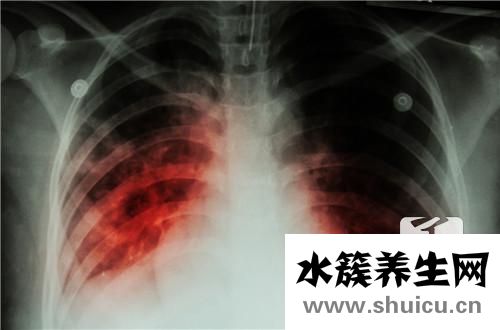

肺結(jié)核病關(guān)鍵根據(jù)呼吸道傳播。肺結(jié)核病的密切接觸者較非常容易被感染。可根據(jù)PPD皮試和結(jié)核抗體查驗(yàn)分辨是不是感染結(jié)核桿菌。

日常生活假如猜疑得了肺結(jié)核,建議應(yīng)當(dāng)立即開展查驗(yàn),此外,也應(yīng)當(dāng)多掌握此病的病癥,肺結(jié)核表現(xiàn)癥狀以下:

(1)原發(fā)性(Ⅰ型):多見于小孩,多沒有癥狀的,有時(shí)候主要表現(xiàn)為低燒、輕咳、流汗、心跳快、胃口差等,極少數(shù)有呼吸音變?nèi)酰伎陕劶捌苫驖裥粤_音。

(2)血液循環(huán)播散肺結(jié)核(Ⅱ型):亞急性粟粒型肺結(jié)核發(fā)病大幅度,有寒顫、高燒,人體體溫達(dá)到40℃以上,多呈弛張熱或稽留熱,血白細(xì)胞計(jì)數(shù)可降低,血沉加快。急性與漫性血液循環(huán)播散性肺結(jié)核現(xiàn)病史較遲緩。

(3)侵潤(rùn)型(Ⅲ型):肺臟有外滲、侵潤(rùn)及不一樣水平的干酷樣變病。大部分病發(fā)遲緩,初期無顯著病癥,后漸出現(xiàn)發(fā)熱、咳嗽、盜汗、胸口痛、削瘦、咳嗽有痰及咯血。血常規(guī)化驗(yàn)由此可見血沉變快,痰結(jié)核桿菌塑造為呈陽性。

(4)漫性化學(xué)纖維裂縫型(Ⅳ型):反復(fù)出現(xiàn)發(fā)熱、咳嗽、咯血、胸口痛、盜汗、食欲不佳等,膈肌形變,病側(cè)膈肌凹陷,肋空隙變小,呼吸運(yùn)動(dòng)受到限制,支氣管向患肢挪動(dòng),吸氣變?nèi)酢?/p>